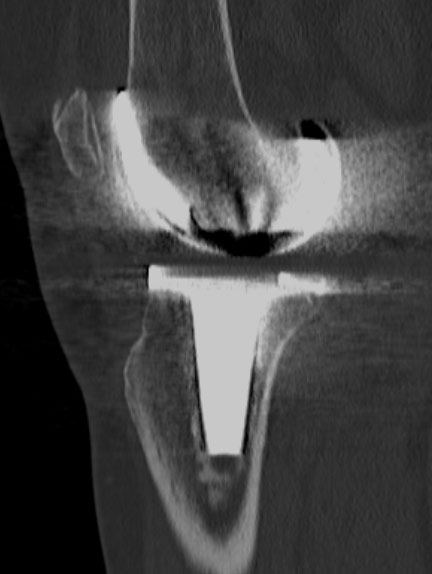

Imaginile cu parametri de os (“kernel” dedicat osului) sunt cu conturi mult mai netede, mai exacte, mai “sharp”, care permite o foarte bună apreciere a celor mai fine traiecte de fractură, însă imaginile 3D obținute pe seama acestora nu sunt la fel utile, fiind cu margini ascuțite și un aspect mai puțin plăcut vizual datorită prea multor detalii prezente.

Reconstrucții în alte planuri (MPR)

Reconstrucții cu parametri speciali